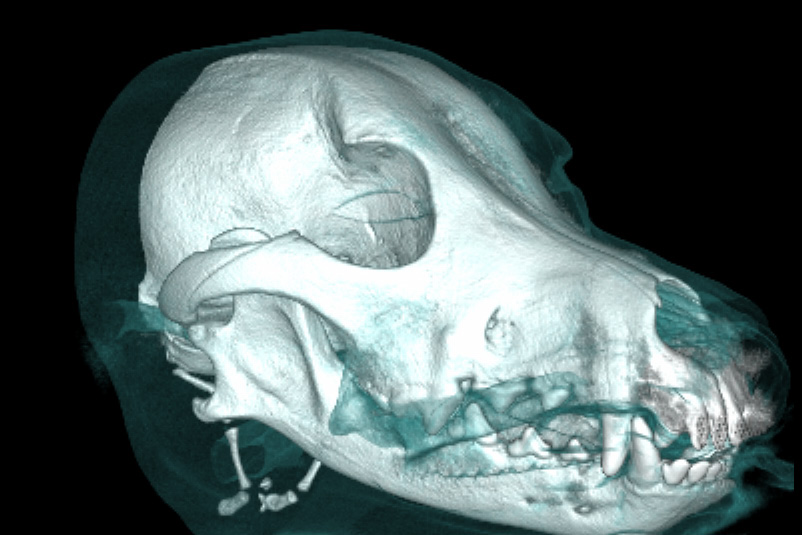

Le scanner fournit des images 3D des structures osseuses des animaux avec une précision d’ordre submillimétrique, ce qui permet d’améliorer le diagnostic et la planification du traitement.

Les couches fines et nettes qu’il est possible d’obtenir au moyen de la CBCT sont plus précises que les radiographies 2D classiques.

Convient aux animaux de toutes tailles, et en particulier aux espèces brachycéphales.

Les images en 3D facilitent la visualisation de l’état et des options pour le propriétaires de l’animal.

Une excellente qualité d‘image

Le scanner Planmed Verity ® VET fournit des images 3D très précises de l’anatomie de l’animal, avec une résolution d’ordre submillimétrique. Ce scanner CBCT a été développé pour détecter les pathologies et les fractures même les plus petites dans les structures osseuses de l’animal. Au moyen du scanner CBCT Planmed Verity VET il est possible d’obtenir des images 3D précises des dents, du crâne et des extrémités de l’animal en vue du diagnostic et de la planification du traitement. Bien que les appareils de radiographie numérique et les échographes soient utiles dans le traitement des patients, ces modalités d’imagerie présentent des limitations fondamentales par rapport à l’imagerie 3D, car elles fournissent des projections bidimensionnelles de l’anatomie tridimensionnelle.